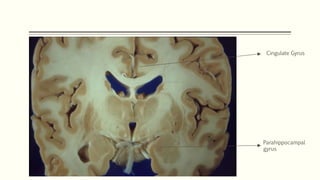

Papez Circuit

Control of emotional expression

Memory storage

Cingulate Gyrus

Parahippocampal

gyrus